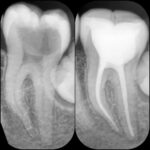

لبخندت را بیمه کن

انجام تمامی درمانهای کودکان و بزرگسالان

بیش از 20 سال تجربه، گواهینامه ایمپلنت از سوئیس، گواهینامه زیبایی و ترمیمی از آمریکا